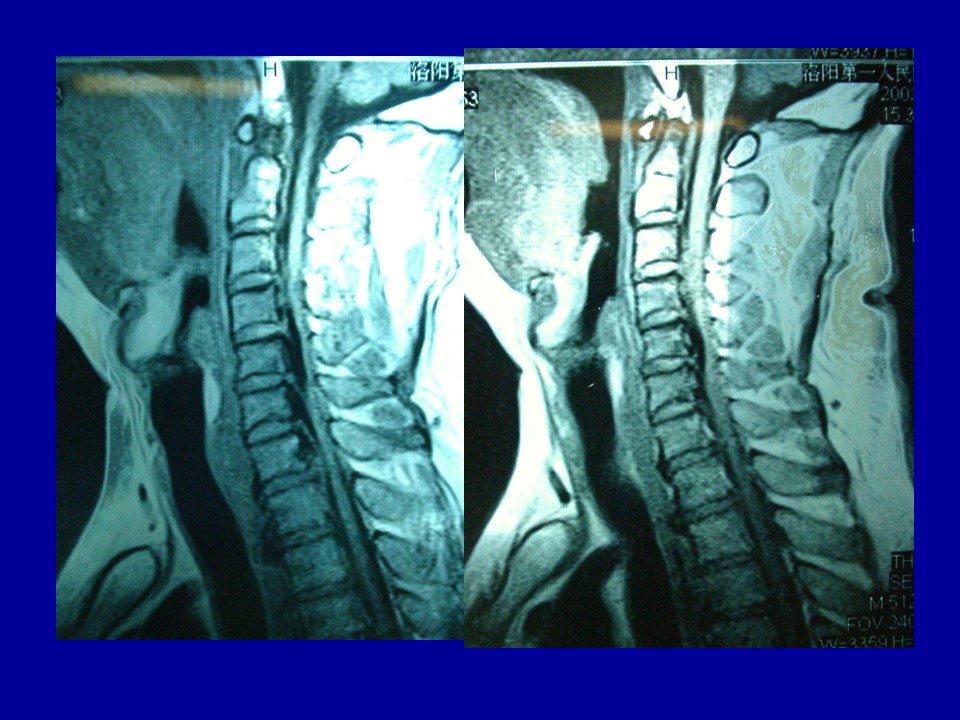

颈椎病的解剖及分型治疗PPT